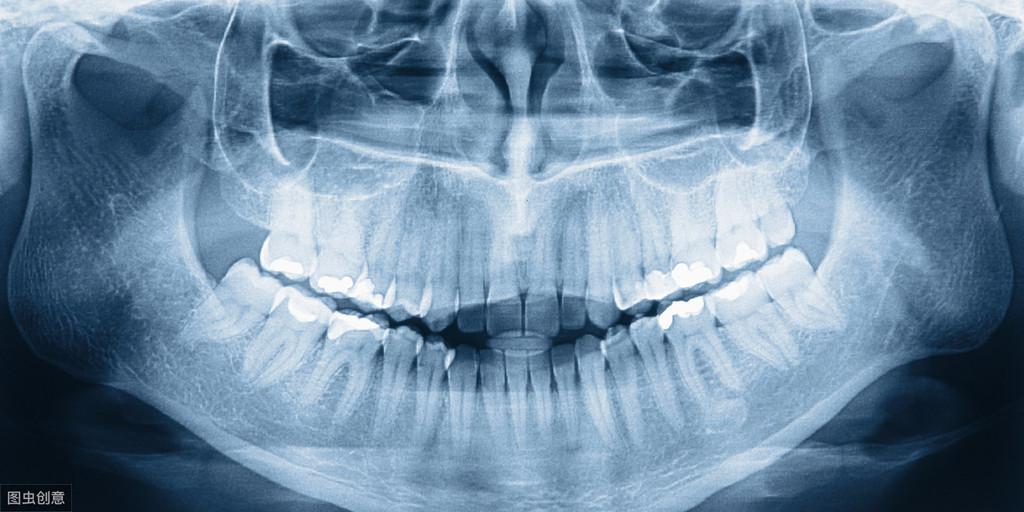

牙齿如果有牙列的拥挤,有牙裂不齐,有中线的偏移或者是有牙缝,或者是有龅牙,或者是有地包天,或者是有开颌等等,都是需要做牙齿的矫正调节的。牙齿矫正的费用,不同的地区费用有所不同,而且不同的矫正方法费用也有所不同,不同的材料费用也有所不同。一般来说,如果是金属托槽矫正,那么费用在15000到18000之间。如果是自锁托槽矫正,那么费用在两万左右。如果是隐形矫正,那么费用大概是在4万到5万元左右,所以说牙齿矫正的价格是有所不同的。很多患者如果有牙齿的错颌畸形,不管费用有多高,我们还是需要做矫正的,否则就有可能造成很多的并发症。。